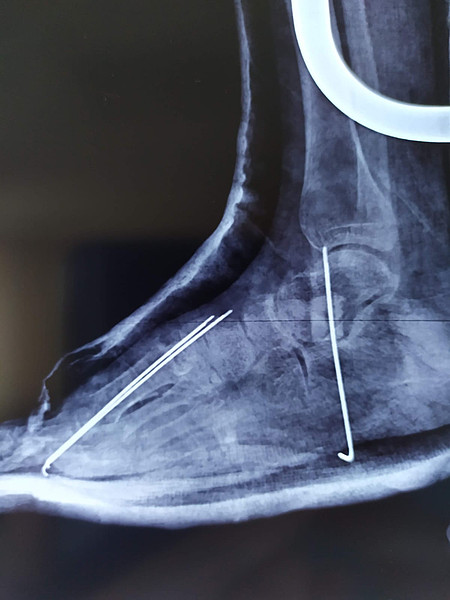

IMG-20230901-WA0003.